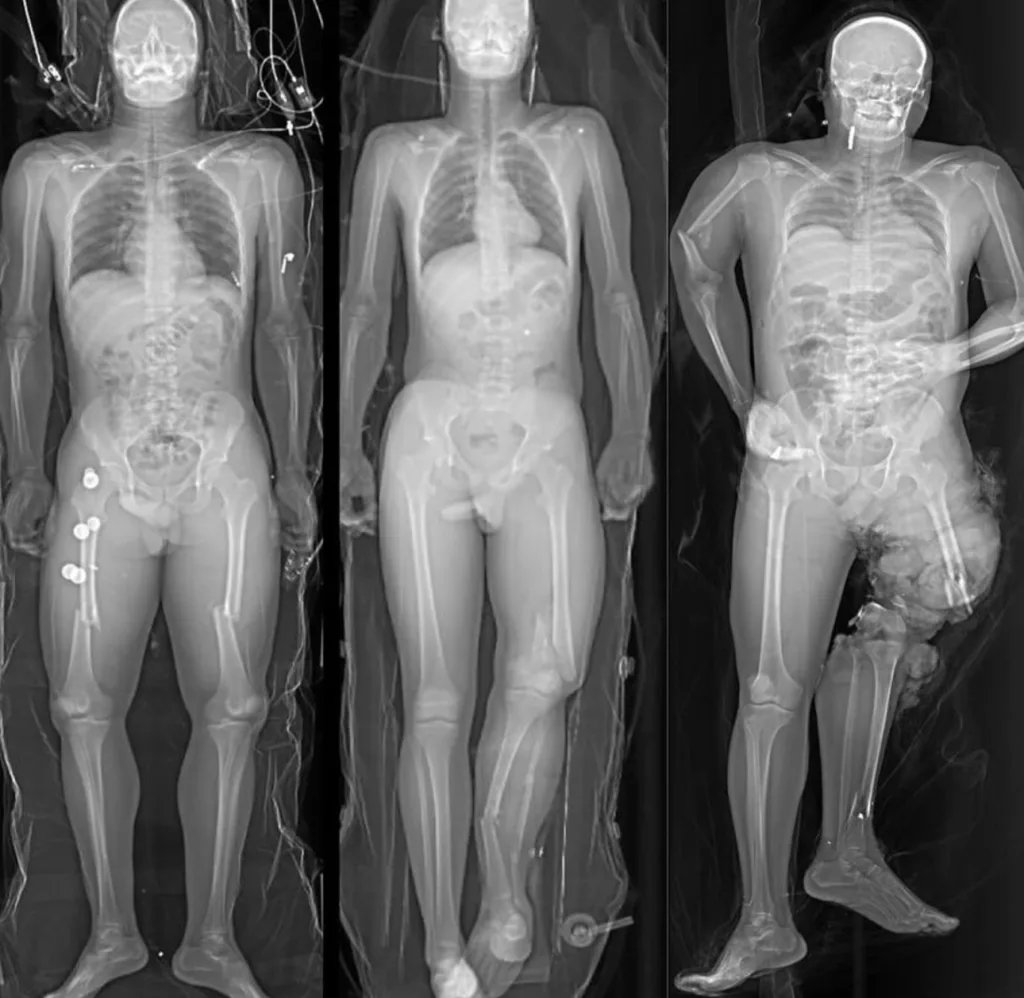

Un mismo accidente… tres hermanos, tres vidas que se apagaron, la siguiente crónica, relata la historia detrás de una radiografía impactante. una radiografía que se volvió viral en internet, porque muestra como quedaron los cuerpos de tres jovenes que sufrieron un aparatoso accidente.

Y comenzaron. acelerar las maquinas a toda velocidad, se adelantaban constatemente unos a otros, luego en una curva todo se volvio una tragedia , uno perdio el control y los otros dos intentaron esquivarlo , al final todos tuvieron un accidente multiple y trafico. La ambulancia llego a toda prisa para brindar auxilio , pero era demasiado tarde ,los tres hermanos ya no tenian pulso. los tres cuerpos estaba sobre el asfalto , inertes en un silencio eterno.